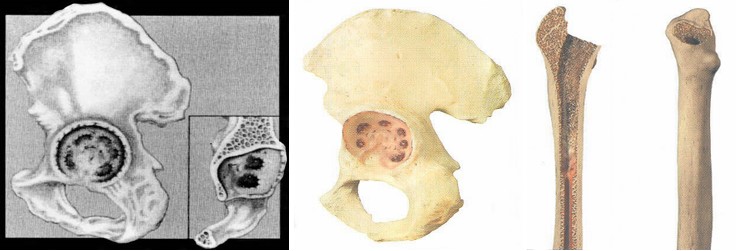

Найважливішою з проблем ревізійного протезування є наявність у хворих дефектів кісткового ложе протеза, як результат гранулематозного запалення, що виникає під дією продуктів зношення та руйнування пари тертя.

В своїй роботі ми класифікацією кісткових дефектів ложе нестабільнокористувалисяго протеза колінного суглоба за AORI (Anderson Orthopaedic Research Institute, USA), 1997 де автори виділяють 3 типа кісткових дефектів

Тип 1 – інтактна кістка (intact metaphysealbone) – невеликі кісткові дефекти, зазвичай без пошкодження кортикальної кістки. Характеризується нормальною кісткової структурою і збереженням губчастої і кортикальної кістки метафиза, нормальним рівнем суглобової лінії. позначаються як F1 – для стегнової кістки і Т1 – для великогомілкової.

Тип 2 – пошкоджена кістка (damаged metaphyseal bone) – характеризується втратою губчастої і кортикальної кісткової маси метаепіфізів, без заповнення якої неможливе створення надійної опори для компонентів ревізійного імплантату і відновлення анатомічного рівня суглобової лінії. (F2 А та F2 Б – для стегнової і Т2 А та Т2 Б – для великогомілкової кісток)

Тип 3 – дефіцит кістки (deficient metaphyseal segment) – характеризується вираженою втратою губчастої і кортикальної кісткової маси метаепіфіза, без компенсації якої неможливе створення опори для компонентів ревізіційного імплантату і відновлення нормального рівня суглобової лінії. Дефекти частіше поширюються до надвиростків і вище на стегнової кістці або до горбистості і нижче на великогомілковій кістці. (F3 А та F3 Б – для стегнової і Т3 А та Т3 Б– для великогомілкової кісток)

Найбільш небезпечними для стабільності чашки ендопротеза є дефекти «даху» . Їх присутність приводить до появи зон перевантаження переднього та заднього країв западини, напруження котрих вп’ятеро перевищують межу її міцності – 270 кГ/см2

При наявних дефектах до 50 см3 є можливість досягти первинної фіксації безцементного ендопротеза або надійної первинної фіксації цементного компонента